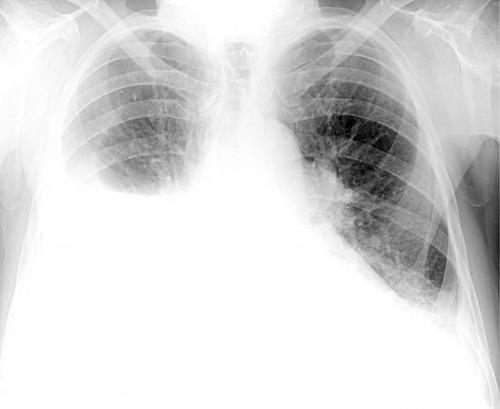

Возникающая в результате нарушения газообмена гипоксия, т. е. кислородное голодание, отрицательно сказывается на работе всего организма, поскольку все органы страдают от нехватки кислорода. На КТ или рентгеновских снимках в таких ситуациях становятся заметными белые пятна, что еще называют эффектом матового стекла. Впоследствии при развитии фиброза на снимках могут визуализироваться особые затемнения, указывающие на пневмофиброз. Хотя подобные изменения характерны не только для коронавирусной инфекции, но и для других тяжелых бактериальных и вирусных пневмоний.

Пневмония - одно из самых опасных заболеваний органов дыхания. Из всех пневмоний - COVID-ассоциированные вызывают наиболее серьезные повреждения. Это связано с тем, что коронавирус приводит к обширному поражению легочной ткани и эритроцитов, из-за чего снижается поступление кислорода в организм и страдают другие органы и ткани: почки, печень, головной мозг, сердце. Даже при легком или бессимптомном течении болезни на компьютерной томографии у пациентов часто выявляются обширные участки повреждения по типу «матового стекла».

По данным открытой научно-исследовательской базы PubMed, наиболее распространенные осложнения после коронавируса (вирусной пневмонии) со стороны дыхательной системы, которые снижают качество жизни и сокращают функциональный объем главного дыхательного органа — это пневмофиброз и другие интерстициальные заболевания легких (ИЗЛ). Прогноз наименее благоприятный у пациентов, которые перенесли тяжелую пневмонию с обширным воспалением (КТ-3 и КТ-4) и диагностированным на КТ симптомом «булыжной мостовой». Выраженность фиброзных изменений может быть небольшой (при КТ-1 и КТ-2) — в этом случае пациент даже не почувствует, что в легких произошли изменения.

Таким образом, у некоторых пациентов, переболевших вирусной пневмонией, вызванной COVID-19 в острой и тяжелой форме, на КТ могут быть выявлены признаки интерстициальных изменений легких, к которым относится и фиброз легких. К радиологическим признакам в данном случае относится усиление легочного рисунка — уплотнение альвеолярных капсул, интерстиция, нарушение структуры легочного матрикса.